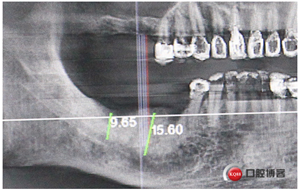

中年男性,右上右下后牙缺失,上頜竇底骨高度3mm,身體健康無不良習(xí)慣。

計(jì)劃:1.右上6,7外提升同期植入植體

2.右下5,6,7種植